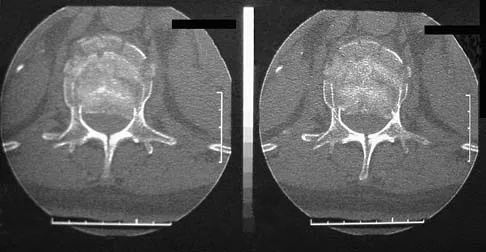

Question 96

Figure 9 shows a cross-sectional view of the spinal cord at the lower cervical level. Injury to the structure indicated by the black arrow will lead to what neurologic deficit?

Explanation